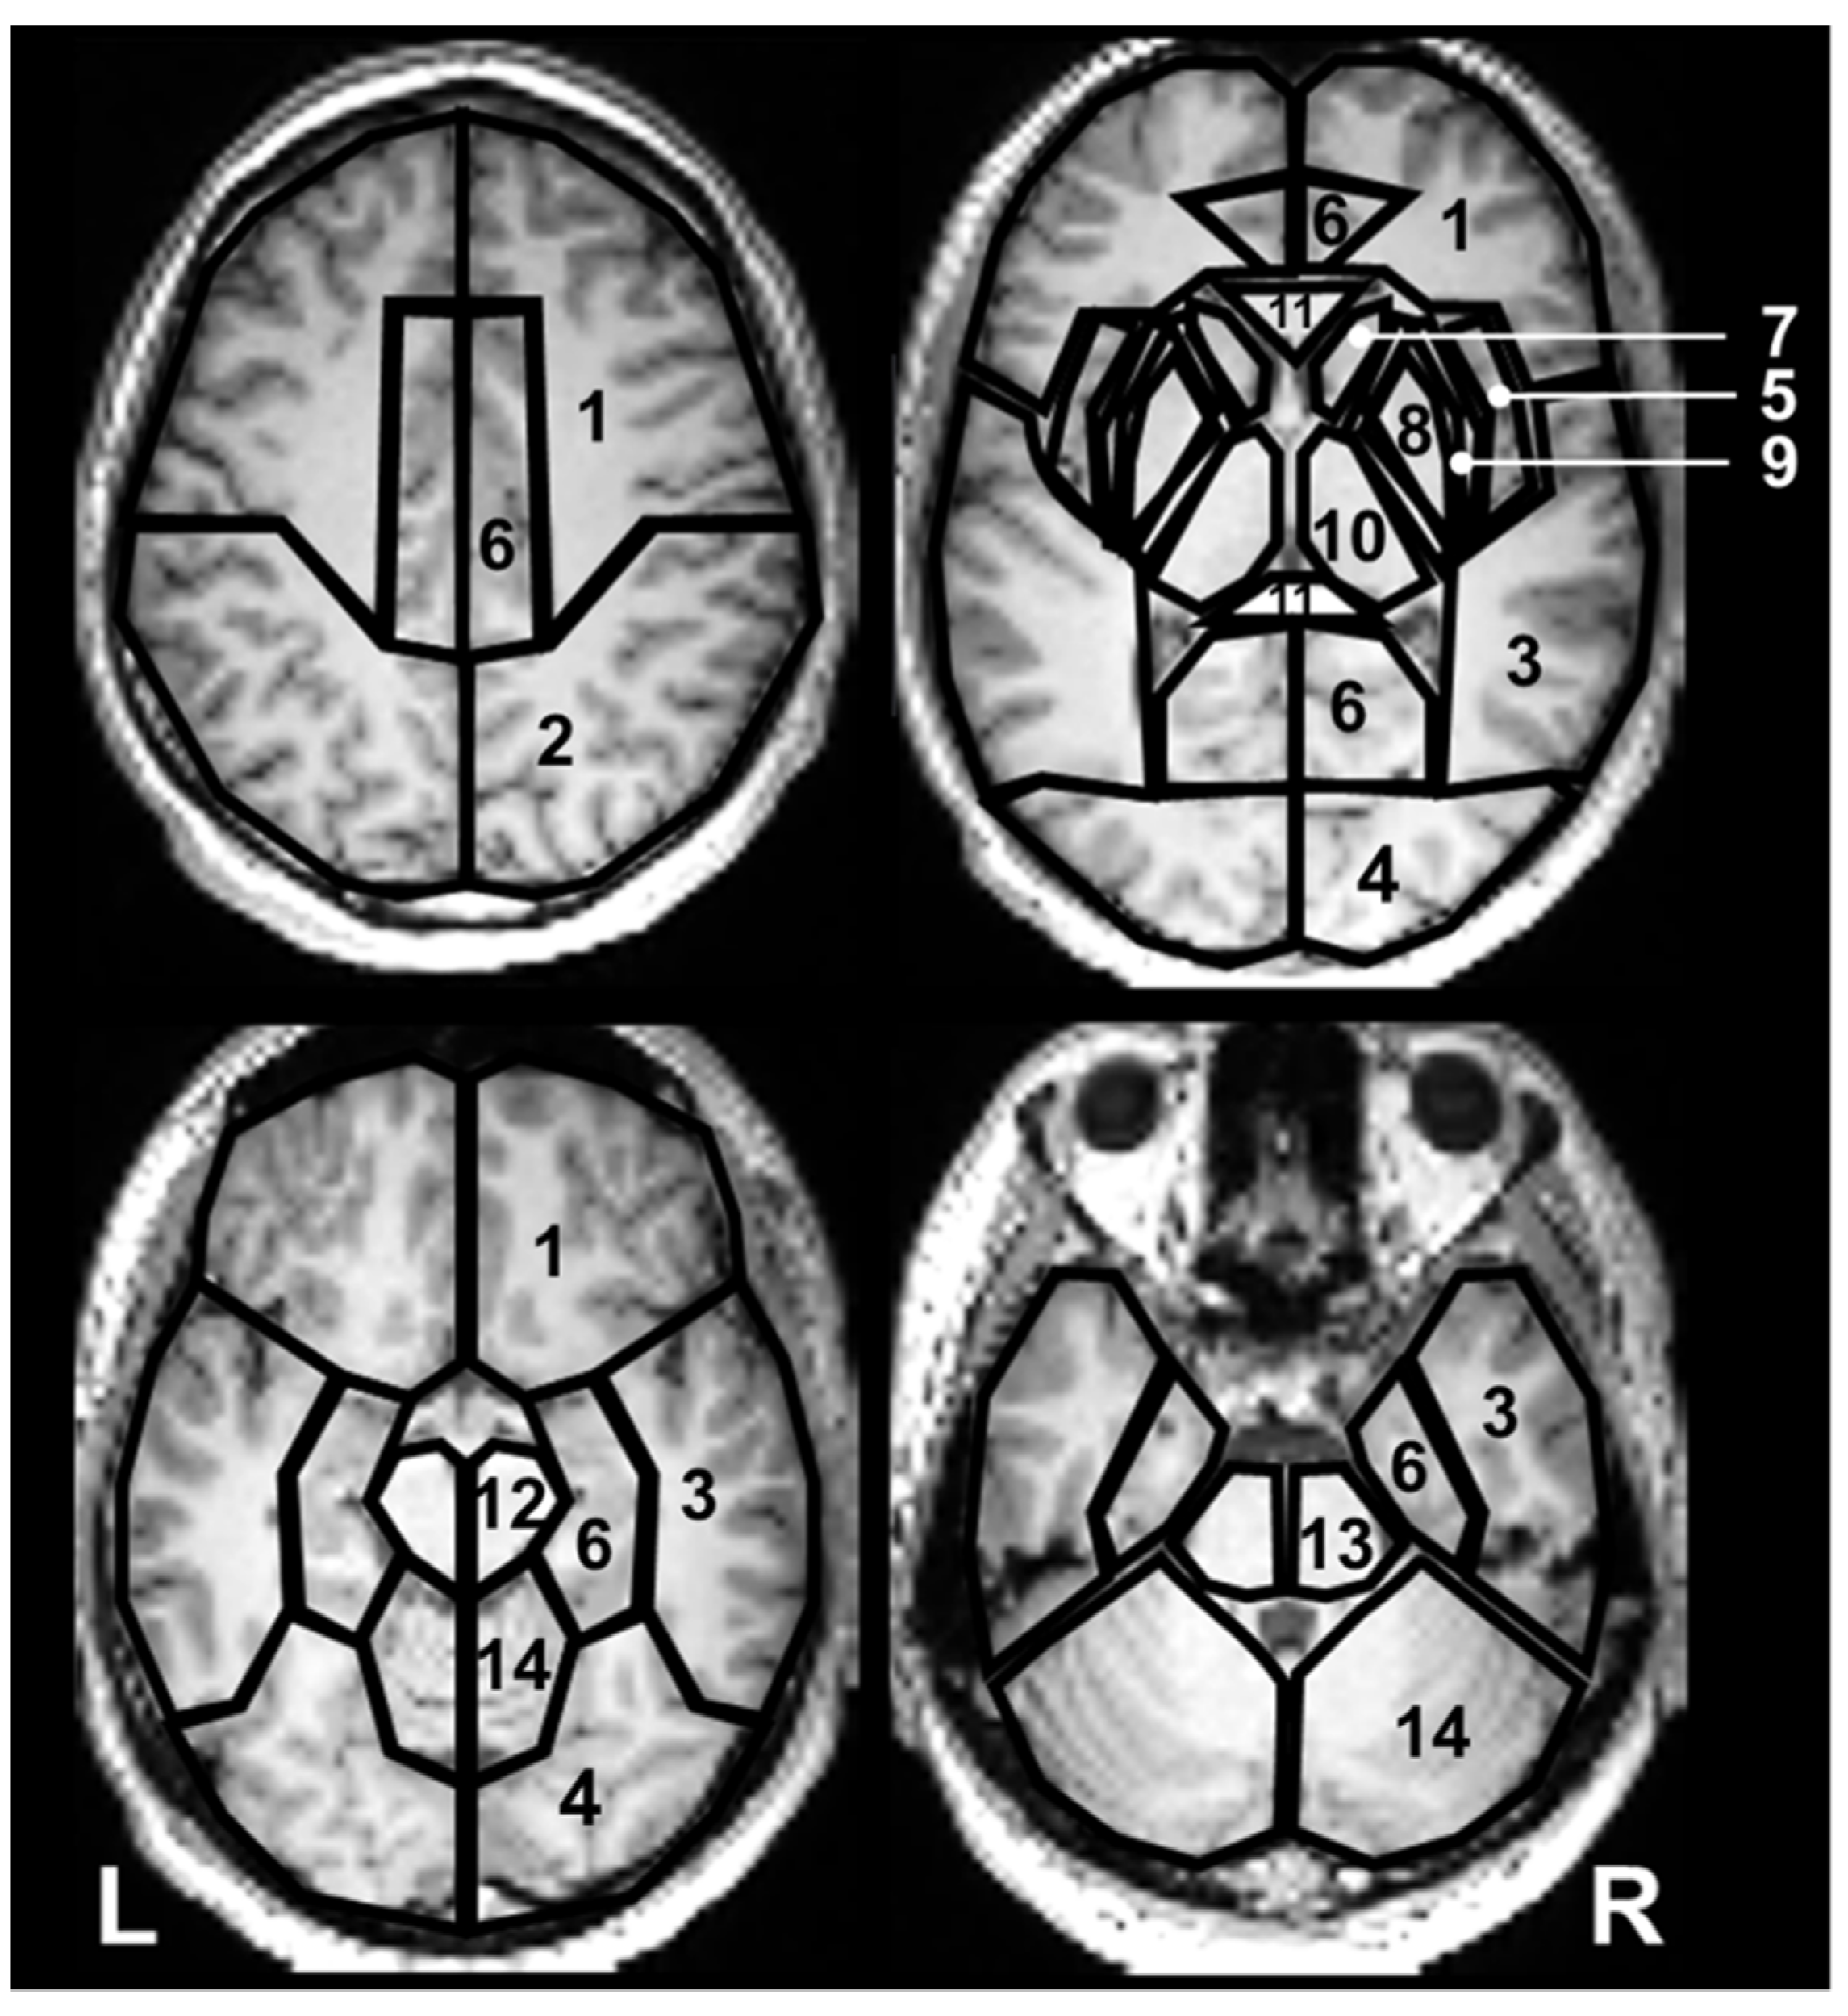

4.2.1. For Evaluation of the Distribution of Major Metabolite Ratios